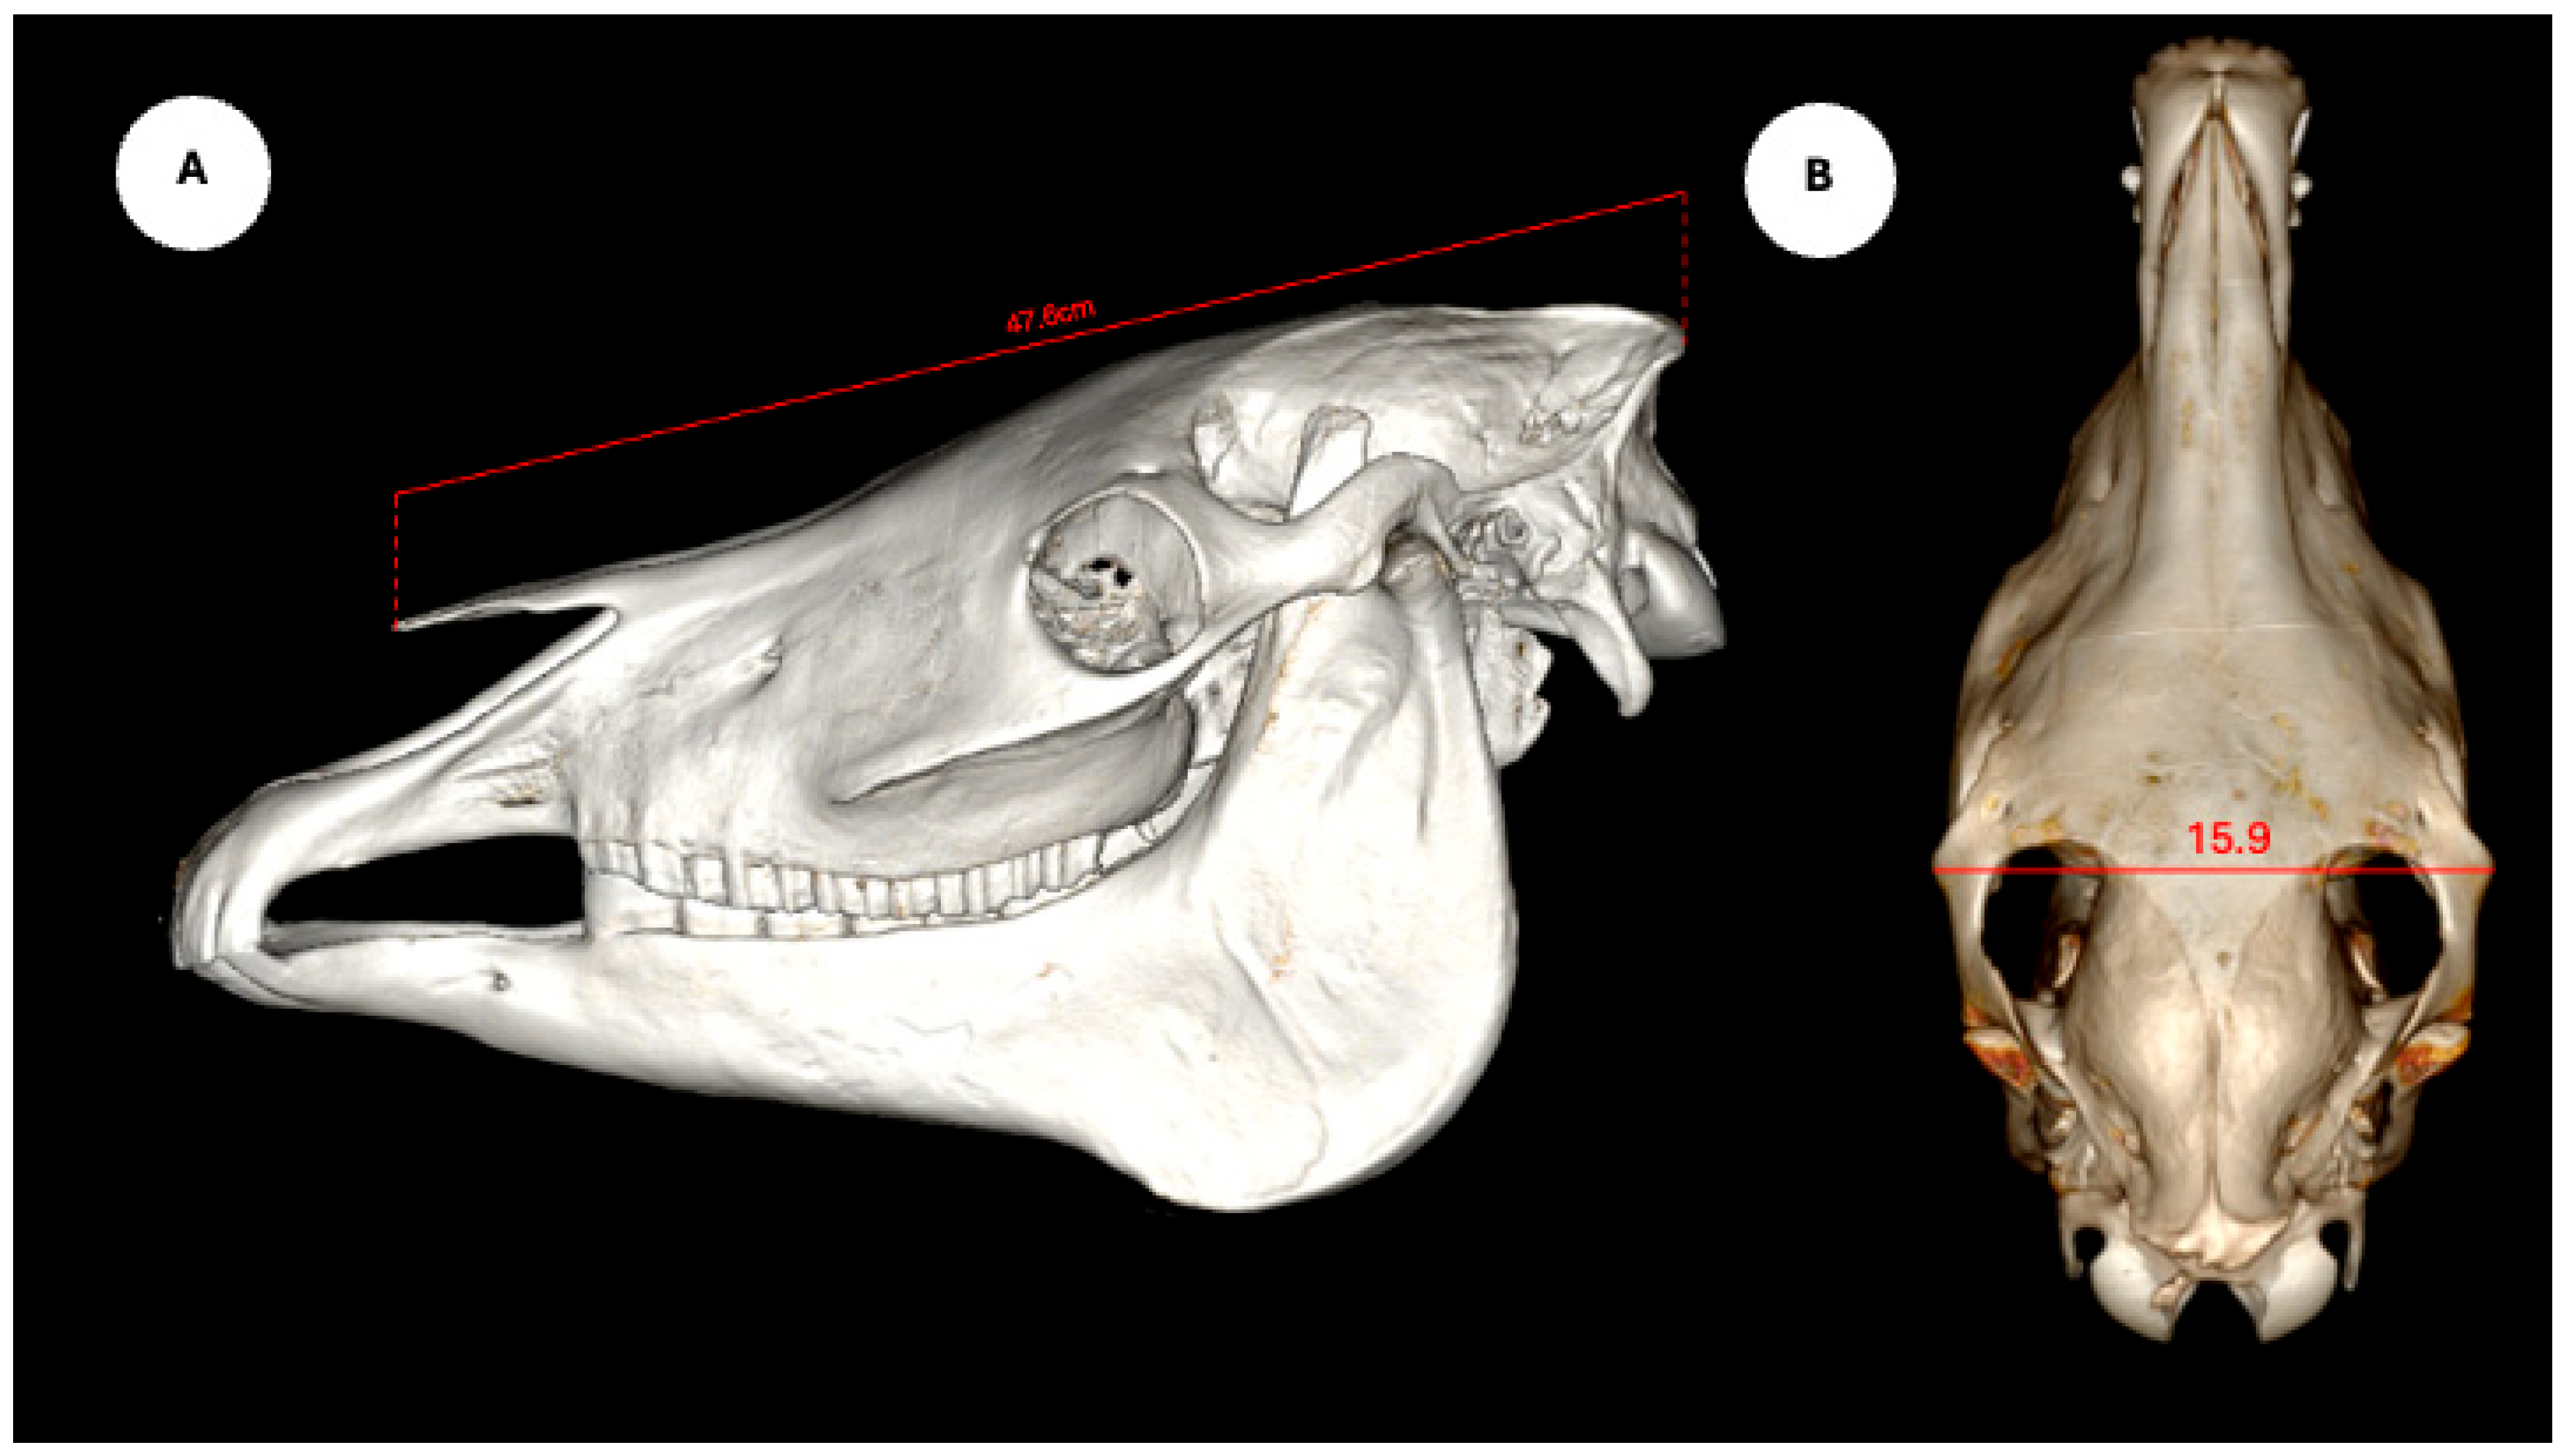

The study also evaluated cranial dimensions by measuring skull length—from the occipital protuberance to the rostral border of the nasal bone (Figure 6A)—and zygomatic width, defined as the distance between zygomatic bone borders (Figure 6B) [12].

Figure 6.

Volume rendered images of the equine skull showing (A) skull length, measured from the external occipital protuberance to the rostral border of the nasal bone, and (B) skull width, measured between the lateral edges of the zygomatic arches.

Descriptive statistics for the study population are summarized as follows. Regarding breed distribution, 20 animals (95.23%) were crossbred, and one (4.76%) was a pure English Horse. In terms of sex, 18 individuals (85.71%) were male and 3 (14.29%) were female. The average body weight was 467.54 ± 34.94 kg (range: 400–530 kg), and the mean age was 17.00 ± 4.99 years (range: 10–25 years). Regarding head measurements, the mean nasal–occipital length was 47.80 ± 2.00 cm (range: 46.5–53.0 cm), and the mean zygomatic width was 17.15 ± 1.25 cm (range: 16.0–20.0 cm).